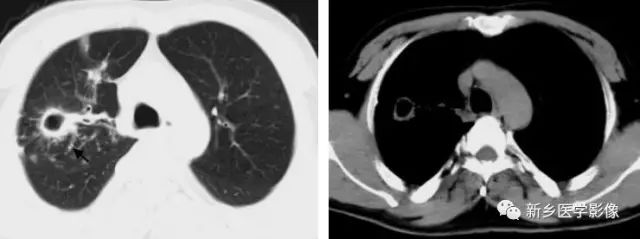

肺结核空洞CT图

a. 肺窗;b.纵隔窗,显示右上肺薄壁空洞(↑)

肺癌空洞CT图

a. 肺窗;b.纵隔窗,显示左上肺厚壁空洞(↑),内壁不规则,见壁结节